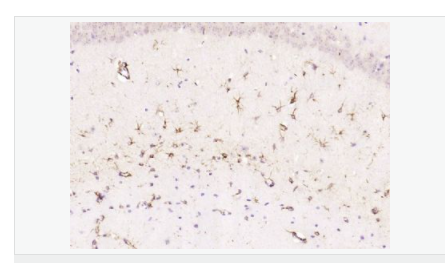

| 產(chǎn)品應用 | WB=1:500-2000 ELISA=1:5000-10000 IHC-P=1:200-1000 IHC-F=1:200-1000 Flow-Cyt=1μg/Test ICC=1:100 IF=1:200-800 (石蠟切片需做抗原修復) not yet tested in other applications. optimal dilutions/concentrations should be determined by the end user. |

| 產(chǎn)品介紹 | This gene encodes one of the major intermediate filament proteins of mature astrocytes. It is used as a marker to distinguish astrocytes from other glial cells during development. Mutations in this gene cause Alexander disease, a rare disorder of astrocytes in the central nervous system. Alternative splicing results in multiple transcript variants encoding distinct isoforms. [provided by RefSeq, Oct 2008] Function: GFAP, a class-III intermediate filament, is a cell-specific marker that, during the development of the central nervous system, distinguishes astrocytes from other glial cells. Subunit: Interacts with SYNM. Isoform 3 interacts with PSEN1 (via N-terminus). Subcellular Location: Cytoplasm. Note=Associated with intermediate filaments. Tissue Specificity: Expressed in cells lacking fibronectin. Post-translational modifications: Phosphorylated by PKN1. DISEASE: Defects in GFAP are a cause of Alexander disease (ALEXD) [MIM:203450]. Alexander disease is a rare disorder of the central nervous system. It is a progressive leukoencephalopathy whose hallmark is the widespread accumulation of Rosenthal fibers which are cytoplasmic inclusions in astrocytes. The most common form affects infants and young children, and is characterized by progressive failure of central myelination, usually leading to death usually within the first decade. Infants with Alexander disease develop a leukoencephalopathy with macrocephaly, seizures, and psychomotor retardation. Patients with juvenile or adult forms typically experience ataxia, bulbar signs and spasticity, and a more slowly progressive course. Similarity: Belongs to the intermediate filament family. SWISS: P14136 Gene ID: 2670 Database links: Entrez Gene: 2670 Human Entrez Gene: 14580 Mouse Omim: 137780 Human SwissProt: P14136 Human SwissProt: P03995 Mouse Important Note: This product as supplied is intended for research use only, not for use in human, therapeutic or diagnostic applications. 星形膠質(zhì)細胞標志物 (Astrocyte Marker) GFAP是一個56kDa的中間絲蛋白(intermediate filament,IF),在中樞神經(jīng)系統(tǒng)發(fā)育期是一個特異性的標志物,以區(qū)別星形細胞和其它膠質(zhì)細胞。GFAP表達在皮層和海馬,急、慢性皮質(zhì)酮治療時表達減少。 GFAP可以和人、大鼠、小鼠的GFAP反應,在正常和腫瘤性的星形膠質(zhì)細胞陽性表達,而神經(jīng)節(jié)細胞、神經(jīng)元、成纖維細胞、少突膠質(zhì)細胞和這些細胞來源的腫瘤細胞陰性表達,主要用于星形膠質(zhì)瘤等中樞神經(jīng)系統(tǒng)腫瘤的診斷和鑒別診斷,GFAP的缺乏可導致AD病。 |